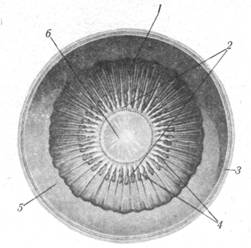

Рис. 2.1. Глазное яблоко (полусхематично, горизонтальное сечение) :

1— передний полюс; 2 — передняя поверхность роговицы;3 —хрусталик;4 — передняя камера глаза; 5 — задняя камера глаза; 6 — ресничные отростки; 7, 30 — связка, подвешивающая хрусталик; 8 — ресничное тело; 9 — ресничная часть сетчатки; 10 — узловая точка;11— боковая прямая мышца; 12 – стекловидное тело; 13— центральная ямка пятна; 14 — углубление диска; 15 — диск зрительного нерва; 16 — центральная вена сетчатки; 17 — зрительный нерв; 18 ~центральная артерия сетчатки; 19— наружное влагалище зрительного нерва;20 — зрительная часть сетчатки; 21 —склера; 22 — собственно сосудистая оболочка; 23— медиальная прямая мышца; 24 — экватор глазного яблока; 25 — зазубренный край сетчатки; 26 — задняяповерхность хрусталика; 27 — кольцо конъюнктивы (обрезана); 28 — ресничная мышца; 29, 31 — радужка; 32 —задняя поверхность роговицы; 33 — роговица; 34— зрительная ось; 35 — наружная ось яблока.

ГЛАЗНОЕ ЯБЛОКО

В глазном яблоке (bulbusoculi) различают передний и задний полюсы. Первый (polusanterior) расположен в центре передней выпуклости глазного яблока. Второй (polusposterior) находится в центре задней выпуклости глазного яблока, несколько кнаружи от зрительного нерва.. Линия, соединяющая оба полюса глаза, является наибольшим его размером (около 24 мм) и называется наружной осью яблока (axisbulbiexternus). Внутренняя ось яблока (axisbulbiinternus) является частью предыдущей, простирается между задней поверхностью роговицы и сетчаткой и равна около 21,3 мм. Эту ось пересекает зрительная ось (axisopticus) — от рассматриваемого предмета к месту наилучшего видения сетчатки. Наибольший поперечный размер глазного яблока, или экватор (equator), равен примерно 23,6 мм. Линии, проходящие через оба полюса перпендикулярно экватору, называются меридианами (meridiani).

Глазное яблоко состоит из оболочек и ядра.

ОБОЛОЧКИ ГЛАЗНОГО ЯБЛОКА

Различают три оболочки: наружную волокнистую, среднюю сосудистую и внутреннюю сетчатую. Волокнистаяоболочка (tunicafibrosabulbi) подразделяется на белочную оболочку, или склеру, и роговицу.

Белочная оболочка (sclera) (рис.2.1), составляющая 5/6 поверхности глазного яблока, состоит из плотных, непрозрачных, белого цвета коллагеновых пучков с примесью эластических волокон. Снаружи в переднем отделе склера покрыта конъюнктивой, а изнутри на всем протяжении ее выстилает эндотелий. В заднем отделе у места образования зрительного нерва склера прободается многочисленными волокнами этого нерва.

Роговица (cornea) представляет собой прозрачную круглую выпуклую кпереди пластинку (толщиной до 1,2 мм ), являющуюся непосредственным продолжением склеры. Она состоит из бессосудистой соединительной ткани и роговых телец, составляющих собственное вещество роговицы (substantiapropriacorneae), к которому прилегают передняя и задняя пограничные пластинки. Передняя поверхность роговицы выстлана многослойным плоским эпителием, а задняя — эндотелием передней камеры глаза. На периферии роговая оболочка граничит с кольцом соединительной оболочки (anulusconjunctivae) (рис.2.1), под которым в толще склеры расположена венозная пазуха (sinusvenosussclerae).

Рис. 2.2. Сосудистая оболочка (внутренняя поверхность):

1 — ресничный кружок; 2 — ресничный венчик; 3 — склера; 4 — ресничные отростки; 5 — сетчатка; 6 — хрусталик.

Сосудистая оболочка (tunicavasculosabulbi) глазного яблока представляет собой густое сосудистое сплетение, пронизанное рыхлой соединительной тканью с множеством пигментных клеток. Эта оболочка разделяется на собственно сосудистую оболочку, ресничное тело и радужную оболочку.

Собственно сосудистая оболочка (choroidea) выстилает изнутри всю склеру, рыхло с ней срастаясь, но несколько не доходит до ее переднего края.

Ресничное тело (corpusciliare) расположено на границе склеры и роговицы (рис.2.1, 2.2), является как бы утолщенной частью собственно сосудистой оболочки. В нем различают ресничный кружок и ресничную мышцу. Ресничный кружок (orbiculusciliaris) представляет собой расположенный по кругу уплощенный валик заднего отдела ресничного тела. Изнутри ресничный кружок переходит в ресничный венчик (coronaciliaris), состоящий из радиально направленных многочисленных (у человека до 70) ресничных отростков (processusciliares) и ресничных складок (plicaeciliares). Эти образования имеют значение в обмене водянистой влаги глаза. Ресничная мышца (m. ciliaris), заложенная в толще ресничного тела, состоит из гладких мышечных волокон меридионального и циркулярного направления. Функция этой мышцы состоит в приспособлении кривизны хрусталика для видения вблизи (мышца натягивает choroidea, что влечет к расслаблению капсулы хрусталика и увеличению выпуклости хрусталика) и вдаль (мышца приходит в исходное положение, в связи с чем капсула хрусталика натягивается и выпуклость хрусталика уменьшается). В возрасте свыше 45—50 лет эта функция (аккомодация) постепенно утрачивается.

Радужка (iris) (рис.2.1, 2.3) является продолжением цилиарного тела и представляется в виде тонкой видимой сквозь роговицу вертикальной пластинки во фронтальной плоскости. В центре радужки имеется отверстие — зрачок (pupilla). В радужной оболочке различают переднюю поверхность, обращенную к роговице, и заднюю, направленную к хрусталику; ресничный край, по которому радужка прикреплена к ресничному телу, и зрачковый край, ограничивающий зрачок. Внутри радужной оболочки имеются гладкие мышцы: суживающая зрачок (т. sphincterpapillae) (круговая) и расширяющая зрачок (т. dilatatorpapillae) (радиальная). При попадании на глаз большого пучка света зрачок суживается, а в темноте расширяется. Цвет радужки зависит от количества пигмента в ней.

Рис.2.4. Строение сетчатки глаза:1— сосудистая оболочка глазного яблока: 2 — пигментный эпителий сетчатки; 3 — палочки; 4 — колбочки; 4а — слой палочек и колбочек; 5 — ядра палочек и колбочек; 5а — внешний ядерный слой сетчатки; 6 — биполярные клетки; 6а — внутренний ядерный слой сетчатки; 7 — ганглиозные клетки; 7а — ганглиозный слой; 8 — аксоны ганглиозных клеток; 8а — слой нервных волокон; 9 — астроцит.

Сетчатая оболочка, или сетчатка (retina) (рис.2.4), выстилает глазное яблоко изнутри и делится на переднюю (меньшую) слепую и заднюю (большую) зрительную части. Границей между этими частями является хорошо видимый на препарате простым глазом зазубренный край (oraserrata). Зрительная часть сетчатки (parsoptica) построена очень сложно, но невооруженным глазом в ней можно различить лишь два слоя: пигментный (stratumpigmenti), плотно срастающийся с сосудистой оболочкой, и мозговой (stratumcerebrate), обращенный в сторону стекловидного тела. Микроскопическое изучение мозгового слоя сетчатки позволяет выделить в нем несколько слоев, содержащих светочувствительные рецепторные аппараты (палочки, колбочки), а также ганглиозные и биполярные клетки.

На внутренней поверхности сетчатки имеется видимый простым глазом небольшой (около 1,5 мм в диаметре) диск зрительного нерва (discus. optici) суглублением в центре. Он является местом, где собираются аксоны ганглиозных клеток сетчатки и, прободая сосудистую оболочку и склеру, образуют зрительный нерв. Область диска лишена светочувствительных элементов (слепое пятно). Несколько кнаружи от диска зрительного нерва заметно округлое (около 1 мм ) красновато-коричневого цвета пятно (macula) — место наиболее острого зрения.

ЯДРО ГЛАЗНОГО ЯБЛОКА

Ядро глазного яблока составляют его светопреломляющие среды: хрусталик, стекловидное тело и водянистая влага передней и задней камер глаза.

Хрусталик (lens) (рис.2.1) имеет форму двояковыпуклой прозрачной линзы, расположенной за радужной оболочкой и зрачком. Задняя поверхность хрусталика более выпукла, чем передняя. Край, где поверхности сходятся, называется экватором. Различают ось хрусталика (длиной в среднем 3,7, при аккомодации до 4,4 мм), соединяющую наиболее выступающие точки (полюсы) обеих поверхностей, и экваториальный диаметр, равный около 9 мм. Хрусталик как бы подвешен к ресничному телу нитевидными связками, которые фиксируются несколько отступив (одни кпереди, другие кзади) от его края. При этом между рядами связок по кругу образуется пространство, заполненное водянистой влагой и широко сообщающееся с камерами глаза.

Тело хрусталика состоит из особого прозрачного бесцветного волокнистого вещества, покрытого прозрачной соединительнотканной капсулой (capsulalentis), которая фиксируется к ресничному телу при помощи поясковых волокон (fibraezonulares). Хрусталик благодаря своей эластичности и функции ресничной мышцы, расслабляющей и натягивающей капсулу хрусталика, изменяет свою форму в зависимости от расстояния до рассматриваемого предмета.

Стекловидное тело (corpusvitreum) (рис.2.1) — студенистая, прозрачная, бесцветная, с малым содержанием блуждающих клеток шаровидной формы масса, выполняющая большую часть полости глазного яблока и покрытая снаружи тонкой стекловидной перепонкой (membranavitrea).

Передняя камера глазного яблока(cameraanteriorbulbi) ограничена спереди задней поверхностью роговицы, сзади передней поверхностью радужки. Задняя камера глазного яблока (cameraposteriorbulbi) ограничена спереди задней поверхностью радужки, сзади передней поверхностью хрусталика и ресничного тела. Обе камеры заполнены водянистой влагой (humoraguosus) и сообщаются между собой через зрачок.